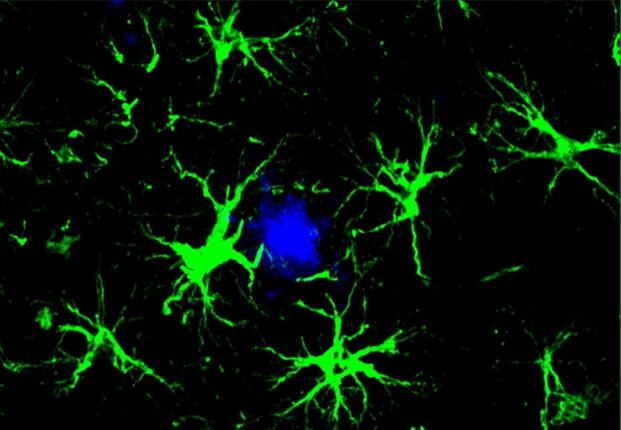

The researchers took T cells from healthy mice, altered them to specifically target amyloid beta, and injected these into six-month-old mice that had been genetically engineered to develop Alzheimer’s-like conditions. The mice received three injections over a span of ten days, after which a notable reduction in amyloid plaques was observed in the treated group compared to controls that received unmodified T cells. Additionally, the brains of the treated mice displayed less activation of microglia and astrocytes, which are linked with the neuroinflammation related to Alzheimer’s.